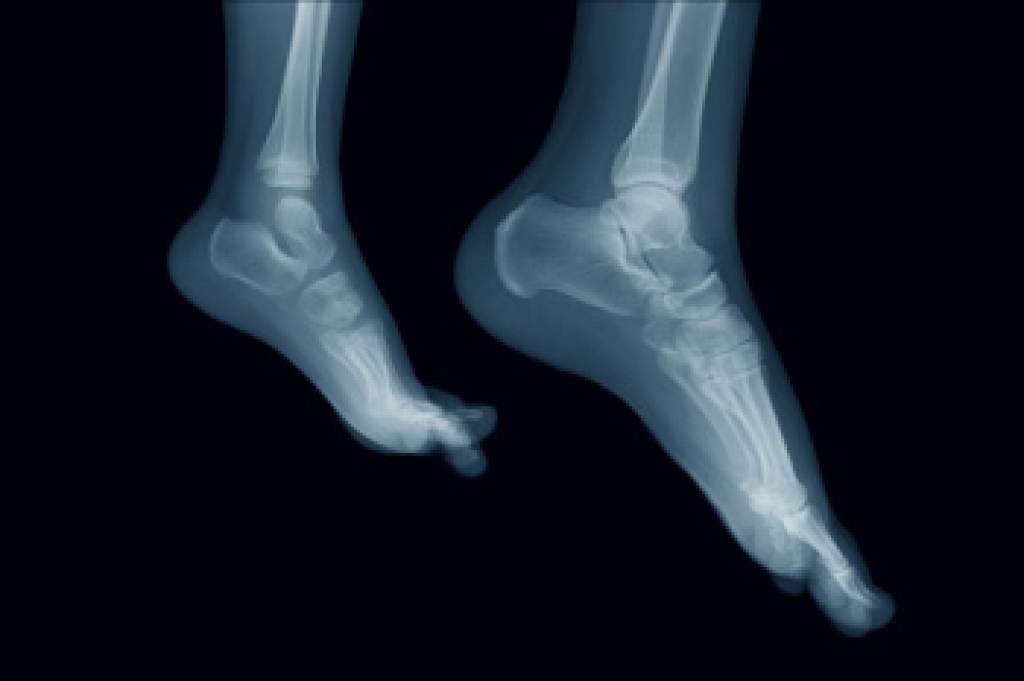

A fifth metatarsal fracture is a break in the long bone on the outside of the foot that connects to the little toe. This injury often occurs after a sudden twist of the foot, a misstep on uneven ground, or direct impact during sports. Patients usually notice sharp pain along the outer side of the foot along with swelling and bruising. Walking may become difficult, and the area can feel tender to the touch. Some fractures occur near the base of the bone and may develop slowly from repeated stress, especially in athletes or active individuals. A podiatrist begins with a careful examination of the foot and reviews how the injury occurred. X-rays are often used to confirm the fracture and determine its exact location. Treatment may include protective immobilization, limited weight bearing, and targeted exercises once healing begins. In certain cases, surgery may be recommended for proper alignment. If you think you may have a foot fracture, it is suggested that you make an immediate appointment with a podiatrist.

A broken foot is caused by one of the bones in the foot typically breaking when bended, crushed, or stretched beyond its natural capabilities. Usually the location of the fracture indicates how the break occurred, whether it was through an object, fall, or any other type of injury.

Those that suspect they have a broken foot shoot seek urgent medical attention where a medical professional could diagnose the severity.

Treatment for broken bones varies depending on the cause, severity and location. Some will require the use of splints, casts or crutches while others could even involve surgery to repair the broken bones. Personal care includes the use of ice and keeping the foot stabilized and elevated.